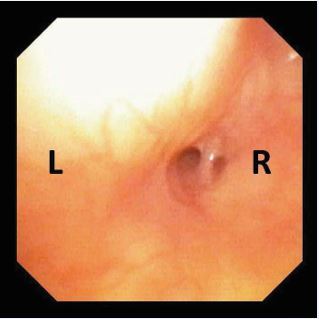

A healthy 2.5-year-old boy presented with five days of fever and cough followed by the development of anterior neck swelling. Physical examination revealed a large, tender, firm mass with slight skin discoloration. US demonstrated a 4×4 cm multiloculated collection within the left thyroid lobe with possible air bubbles. CT showed an extensive inflammatory process with a collection extending toward the left pyriform sinus, posteriorly abutting the esophagus, and causing rightward tracheal deviation and left jugular vein compression (Figure 6A,6B). The child underwent drainage under general anesthesia. Flexible laryngoscopy performed within two days confirmed the diagnosis of a fourth branchial cleft sinus by visualizing the tract opening in the pyriform sinus.

Figure 6 (A) Sagittal CT showing inflammation and edema involving the subcutaneous fat of the anterior neck. (B) Coronal CT showing compression of the left jugular vein and rightward tracheal deviation.